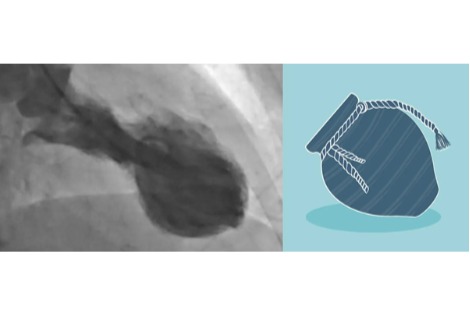

في عام 2023، حاول باحثون في جامعة بنسلفانيا استخدام كبد خنزير معدل وراثيًا كجهاز احتياطي، حيث تم توصيل العضو خارجيًا بشخص توفي مؤخرًا. وتمكن الفريق من تدوير دم الشخص من خلال كبد الخنزير، وهي خطوة نحو استخدام العضو للقيام مؤقتًا بمهام الكبد لدى مرضى فشل الكبد. وفي الحالة الجديدة، أدخل الجراحون الكبد إلى داخل الجسم. بدأ الفريق بخنزير باما مصغر، حُذفت منه بعض جينات الخنزير، وأُضيفت إليه جينات بشرية. تلعب هذه الجينات دورًا في رفض عملية الزرع؛ وكان الهدف من هذه التعديلات تقليل احتمالية فشل عملية الزرع.

وضع الجراحون الكبد المعدّل داخل جسم المتلقي، ووصلوه بأوعيته الدموية، ثم راقبوه لمدة 10 أيام. احتفظ كبد الخنزير بوظائفه، وتدفق الدم بسلاسة، ولم يلحظ فريق وانغ تراكمًا للخلايا الالتهابية، وهو ما يُشير إلى تقبّل المتلقي البشري لعملية الزرع. بعد التجربة، أُعيد جثمان المتلقي إلى عائلته.

يشير فاجيفي إلى أن الجراحة لم تكن عملية زرع نموذجية. لم يقم الفريق باستبدال كبد الشخص، كما يحدث عادةً في عمليات زرع الكبد. بل كان كبد الخنزير كبدًا مساعدًا، موجودًا داخل الجسم إلى جانب الكبد الأصلي. ومؤخرًا، أجرى فريق وانغ عملية زرع كبد كاملة من خنزير إلى إنسان، حيث استبدلوا كبد شخص آخر ميت دماغيًا بكبد خنزير معدّل وراثيًا. أُجريت عملية الزرع في يناير، ويعتزم الباحثون نشر نتائج البحث في منشور مستقبلي، وفقًا لما ذكره وانغ في الإحاطة الإعلامية.